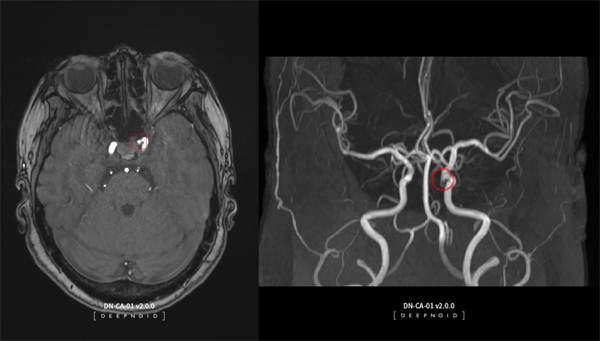

딥뉴로는 뇌동맥류 의심 환자의 뇌혈관 자기공명혈관조영술(이하 MRA) 영상에서 뇌동맥류 의심 부위를 인공지능(AI)로 판독 및 분석해 의료인의 진단을 보조하는 제품이다.